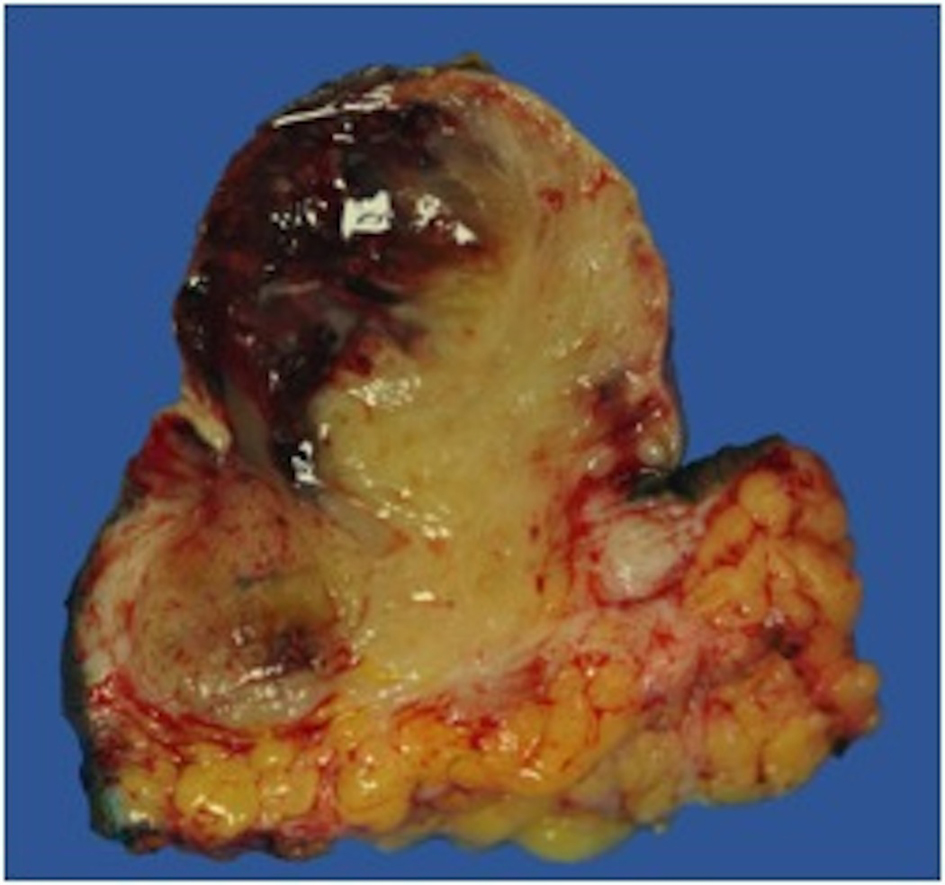

On gross examination, the biopsy specimen had a shiny appearance suggesting myxoidal features along with other areas of hemorrhage (Fig. 4). On histopathological examination (Fig. 5, 6), the specimen again revealed myxoidal features with small round blue cells and other areas of spindle cells arranged in a wavy streamline pattern. There were also areas of high mitotic activity. Histochemically, the specimen stained positive for vimentin and CD99. It stained diffusely positive for S100 and had patchy staining for NSE. It stained negatively for CD31, CD34, desmin, melan-A, SMA, pan-keratin, EMA, CD45, CD56, chromogranin, and synaptophysin.

![]() Click for large image | Figure 4. Gross resected tumor with fatty and myxoidal features and focal hemorrhage. |